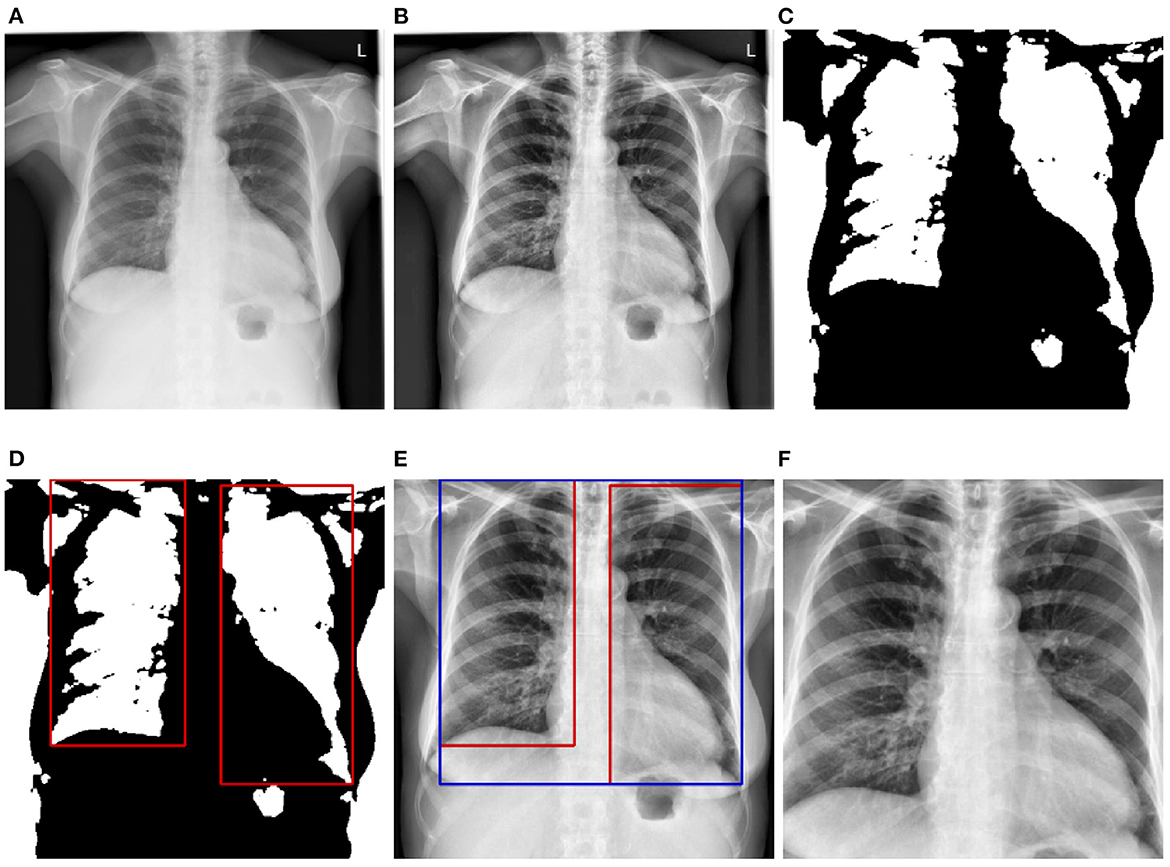

Before being fed into the designed neural networks, CXRs have to be pre-processed in order to significantly reduce the amount of noise within the images, which hinders an optimal optimization of the parameters of the neural networks, resulting into overall sub-optimal classification performances. Moreover, since the data used for the evaluation of the trained deep neural networks stem from another domain, the pre-processing steps also help homogenizing the structure of the data at a certain extent (since the data stemming from both source and target domains go through the exact same pre-processing steps). In the current work, the pre-processing consists of localizing and extracting the chest cavity from each CXR and subsequently using this specific area to perform the evaluation of the proposed approaches. First, CXRs are converted into gray-scale images (see Figure 2A). Secondly, histogram equalization is applied on the resulting images in order to enhance the images' contrasts by applying the contrastive limited adaptive equalization (CLAHE) approach (Zuiderveld, 1994) (see Figure 2B). The resulting images are filtered using a 3 × 3 Gaussian filter. Further noisy details appearing at the edges of the CXRs are also filtered out by zooming into the images with a range set as follows [0.1, 0.1]. Furthermore, a binarization of the filtered images is performed, followed by the application of a set of morphological transformations (erosion and dilation) using a 3 × 3 kernel in order to generate masks over the lungs in the CXRs (see Figure 2C). The contours of the masks are subsequently computed and bounding rectangles around the resulting contours are generated (see Figure 2D). The extreme points of the bounding rectangles are subsequently used to generate a bounding rectangle identifying the chest cavity (see Figure 2E). This specific area of interest is subsequently cropped out of each cxr (see Figure 2F), resized to the shape 299 × 299 × 3 (the number of channels is obtained through the duplication of the cropped CXR by the corresponding amount), and constitutes the input for the designed deep neural networks.

Figure 2

CXR pre-processing steps. (A) Grayscale CXR. (B) Histogram equalized CXR. (C) Binarized CXR. (D) Lungs localization. (E) Area of interest localization. (F) Cropped area of interest (pre-processed CXR).